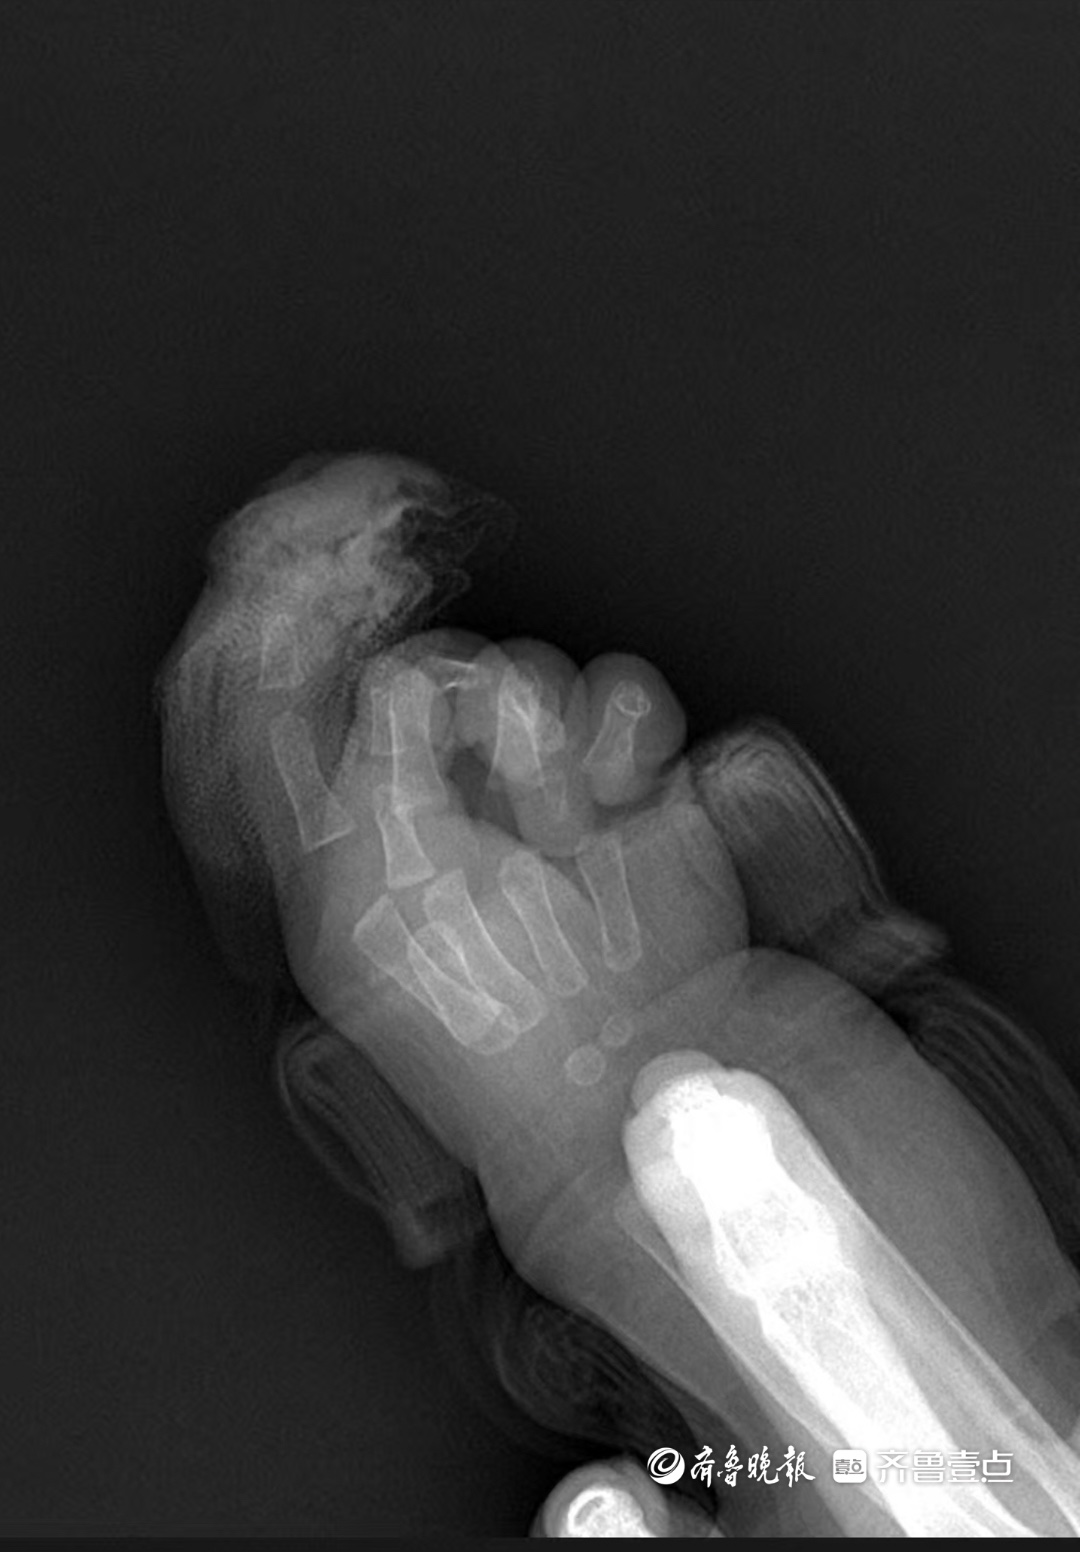

“急诊就诊时间是9时22分,同步启动术前准备。”手及上肢外科主治医生王思月回忆,急诊团队第一时间为芙芙止血、抽血、做心电图和拍片,“孩子伤口还在渗血,更换了3次纱布,同时输液,避免脱水。”

按医院流程,断指被立即送至手术室专用冰箱冷藏。“家属拿来时保存得很好,低温能让细胞代谢速率降低至常温的1/10,为再植争取时间。”王思月说,这是他工作十几年遇到的最小断指再植患者,“整个科室都很重视,从急诊到病房,所有环节都在提速。”

“手术是4月4日下午1点开始的,5点前结束,历时3个多小时。”手及上肢外科主任胡亮回忆。为小婴儿接上断指部位的血管和神经是“显微镜下的极限挑战”。

“最困难的是血管太细,直径不足0.5毫米,仅为成人的1/5。”王思月说,他需用比发丝还细的显微缝线,在20倍显微镜下精准缝合6-8针,“间距误差不能超过0.1毫米,神经和肌腱也得一一吻合,还有细如牙签的钢钉固定指骨,不能损伤骨骺板。”